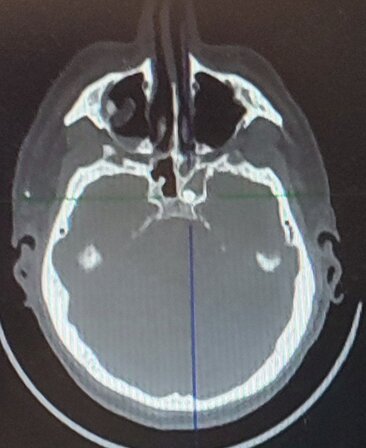

Клинический пример. Раненый П. с огнестрельным слепым ранением средней зоны лица и инородным телом клиновидной пазухи. По результатам КЛКТ головы выявлено инородное тело металлической плотности в левой половине клиновидной пазухи. Под общей анестезией эндоназальным доступом с помощью эндовидеоскопической техники через переднюю стенку выполнено удаление инородного тела. Операция прошла без осложнений.

Компьютерные томограммы раненого в трех проекциях с инородным телом клиновидной пазухи: